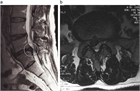

1. 馬尾型もしくは混合型の腰部脊柱管狭窄(LSS)による間欠跛行患者にはリマプロスト投与を推奨する(推奨度2)

1. 保存療法無効例のLSSによる間欠跛行患者では除圧術を推奨する(推奨度2)